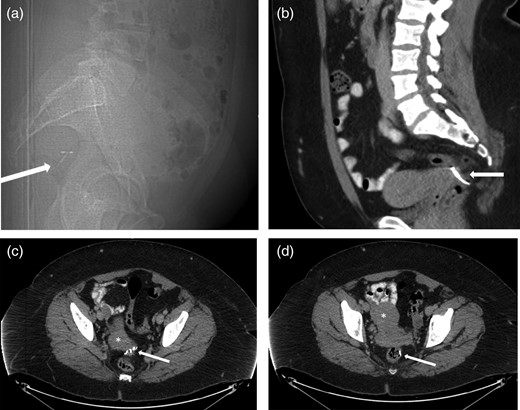

A 37-year-old woman had an IUD inserted 1 year after her only pregnancy. The patient experienced post-procedural bleeding. At her follow-up, the strings of the IUD were not visualized, which was suspicious for IUD migration. An attempt at laparoscopic retrieval was unsuccessful. A computed tomography (CT) scan showed migration of the IUD with the T-arms of the device seen posterior to the left vaginal fornix with the shaft within the lower rectum (Fig. 1). A general surgeon was subsequently consulted, and a diagnostic flexible sigmoidoscopy was performed, which demonstrated protrusion of the IUD into the rectal lumen. The patient was then referred to a colorectal specialist.

(a) Sagittal CT Scout view shows IUD (arrow) in very posterior location, probably within the rectum. (b) Sagittal contrast-enhanced CT of the pelvis showing the extra-uterine position of the contraceptive device (arrow) posterior to the uterus. (c) Axial contrast-enhanced CT of the pelvis reveals extra-uterine position of the contraceptive device arms (arrow) posterior to the cervix (*). (d) Axial contrast-enhanced CT of the pelvis showing the extra-uterine position of the stem of the contraceptive device within the rectal lumen (arrow) after perforating the uterus (*).

An magnetic resonance imaging (MRI) performed 1 month following the original CT demonstrated the T-arms of the IUD to have migrated within the rectum ∼10–12 cm above the anorectal junction at or just above the peritoneal reflection.